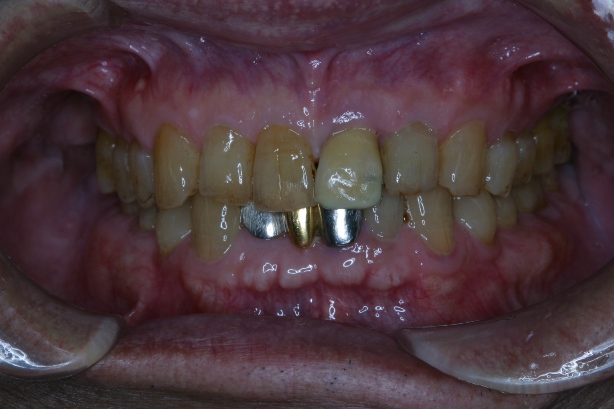

「8020運動」 表彰に出て頂いた方々のお口を拝見